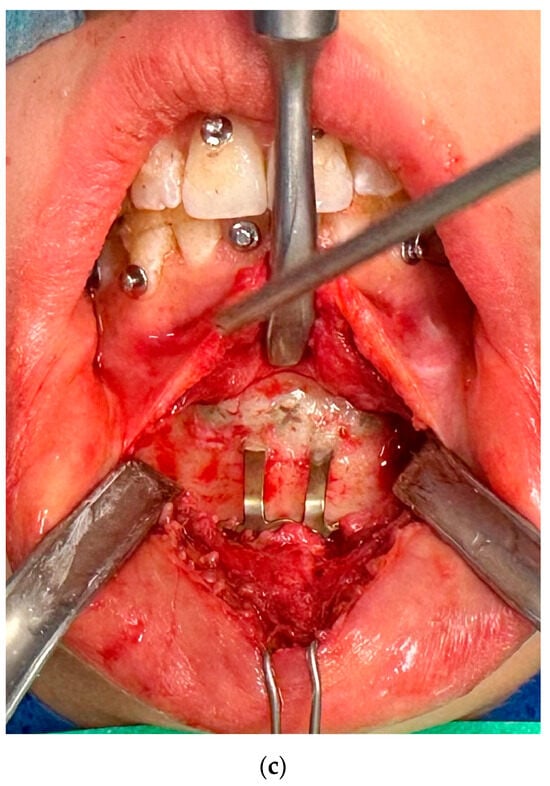

The length of the surgical procedure was also influenced by the fact that in some cases, the fixation hardware was covered with a layer of bone tissue of different thickness and it was necessary to clean the screw slots, which required additional time and, as a result, prolonged the time of surgery (Figure 5).

Figure 5.

(a–c) Images of osteosynthesis covered with a layer of bone tissue.

This situation was recorded in 15 cases. In 11 cases, it was related to osteosynthesis in the mandible.